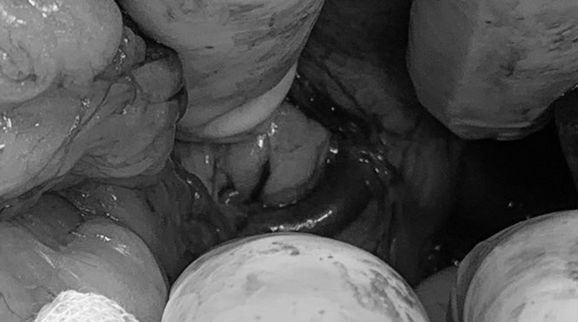

PSS

강아지 PSS(Portosystemic Shunt)는 어린 강아지에서 발생하는 대표적인 선천적 간질환입니다. 정상적인 아이들은 소화 장기에서 나온 혈액이 간문맥을 통해 간으로 들어가 영양분 저장 및 해독 과정을 거친 뒤 대정맥을 통해 전신혈관으로 들어오게 되지만, 이 PSS를 가진 아이들에게서는 이 과정을 거치지 않은 혈액들이 바로 대정맥으로 들어오게되면서 여러 증상을 유발하게 됩니다. 대표적으로 성장 지연, 간헐적 소화기 증상 (잘 안 먹고, 구토, 설사해요), 간수치 상승, 발작 등 신경증상 등이 나타나게 됩니다. 확진을 위해서는 CT 촬영이 필요하며 수술적 교정이 가능한지 판단 후 내과적 치료 및 외과적 치료에 들어가게 됩니다. 본원에서는 약물 관리 및 처방, 진료 상담을 위한 내과 수의사, 간초음파 및 CT 판독을 위한 영상 전담 수의사, 다양한 간담도계 수술 경력의 전담 외과 수의사, 중환자 케어를 위한 24시간 중환자실 운영을 통해 많은 PSS 환자들을 케어하고 있습니다.